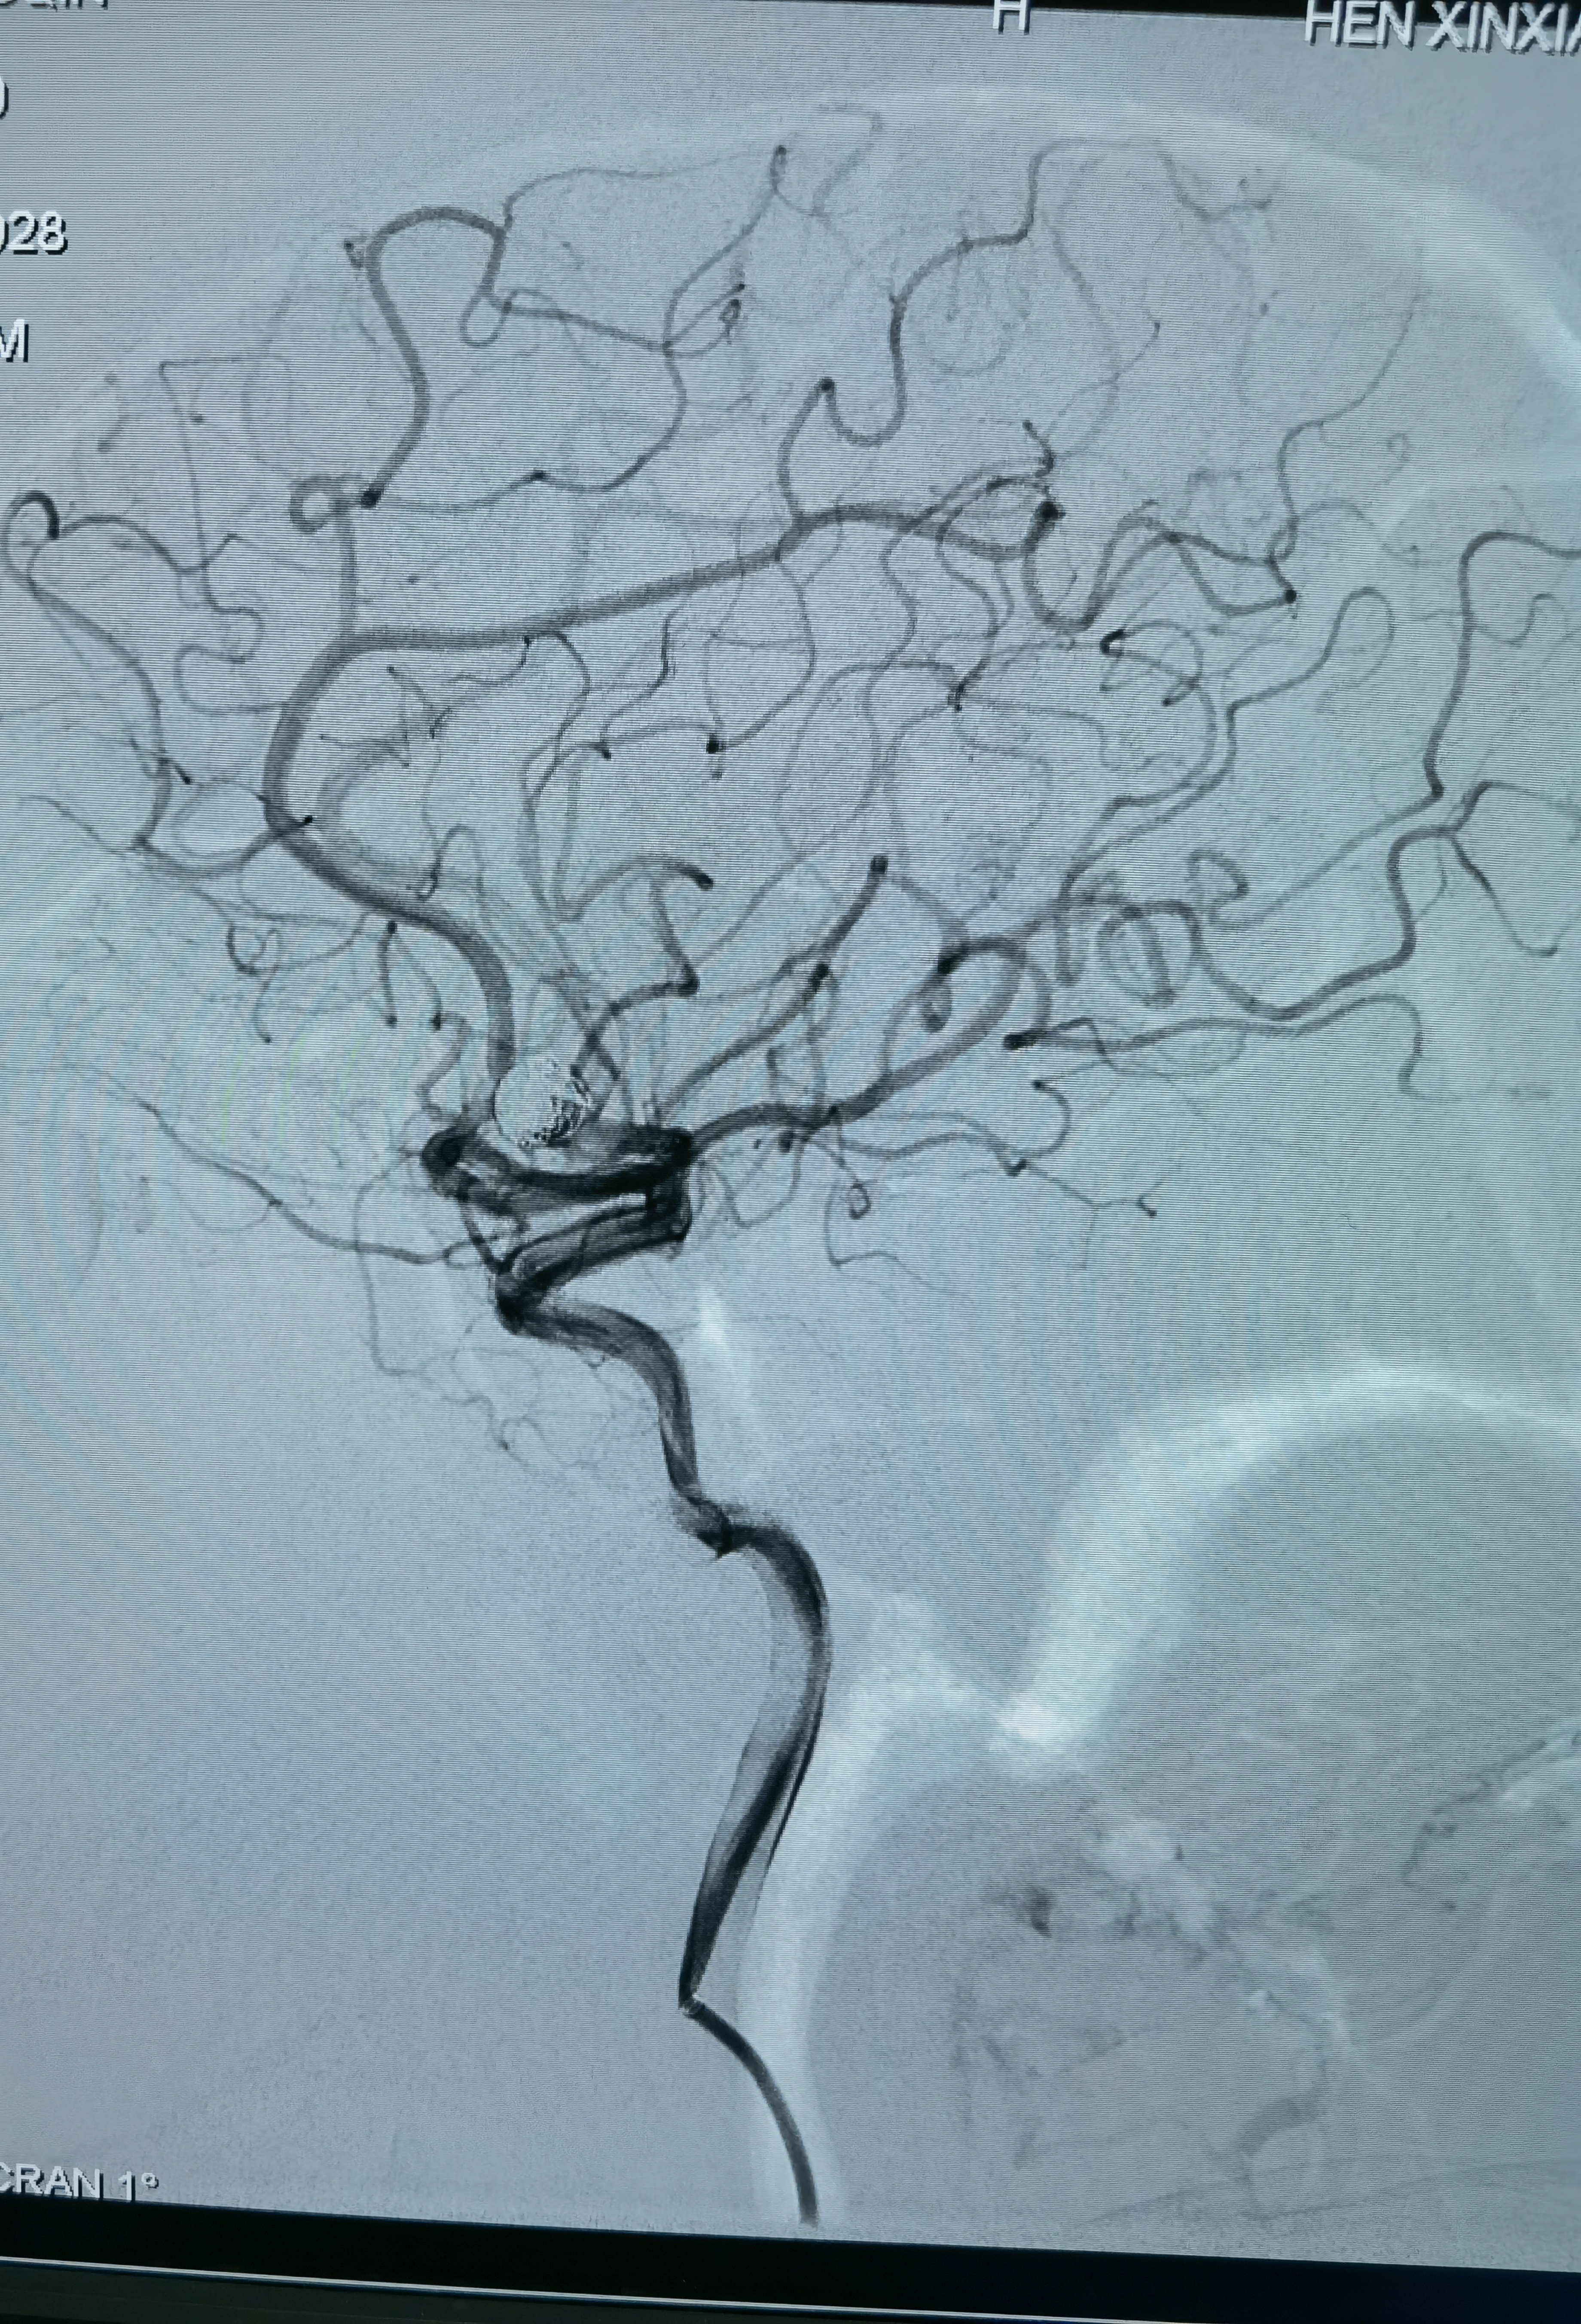

女性,63岁,体检发现动脉瘤,造影显示动脉瘤带子囊,破裂风险大,手术干预!

正位造影